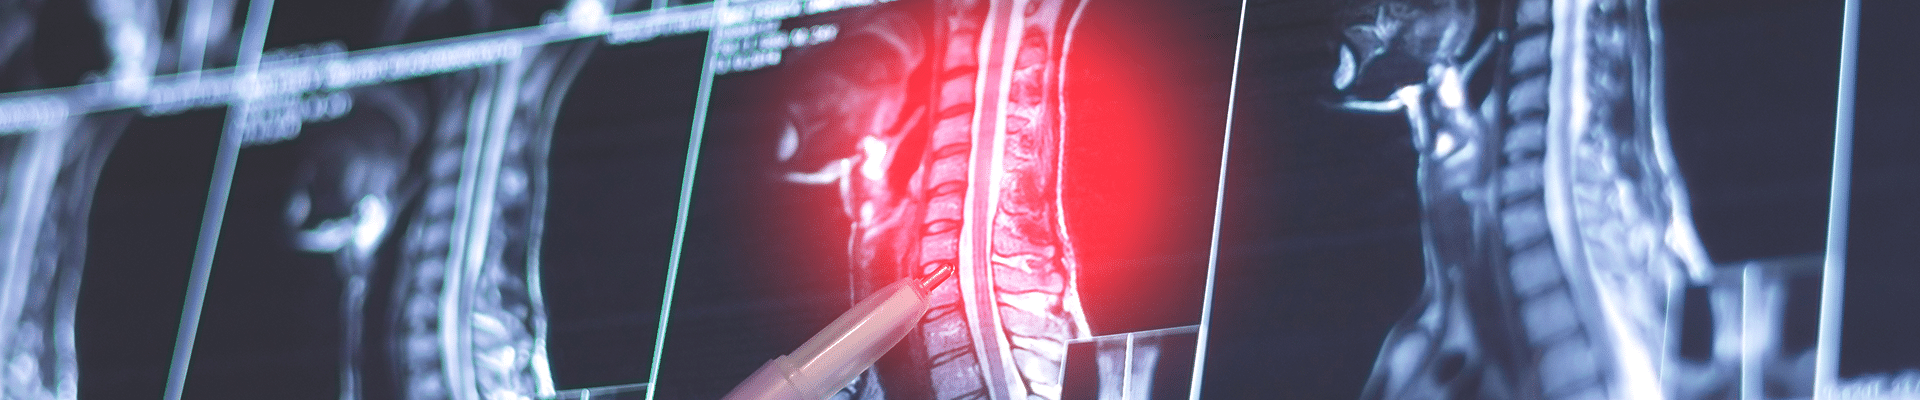

Symptoms that may indicate candidacy for ACDF include significant arm pain (often with neck pain), as well as numbness or weakness in the arms or hands. Diagnostic tests such as MRI, CT scan, and/or myelogram help confirm the presence of a herniated or degenerative disc.

If you have a herniated disc or a degenerating disc in your cervical spine—the seven vertebrae that make up the neck—the odds are good that either the spinal cord or the nerve roots exiting the spine are receiving unwanted pressure from the failing disc. This often leads to chronic neck pain that can radiate into the shoulders, arms, and hands, along with numbness, tingling, or weakness.